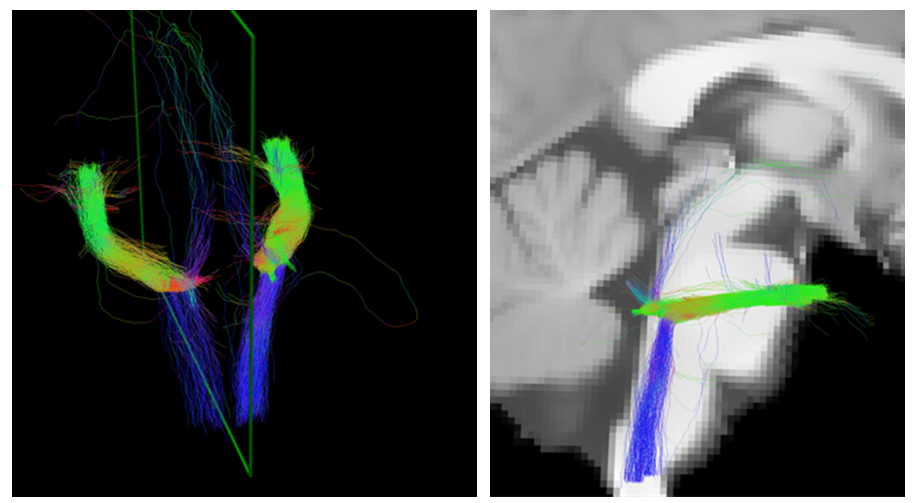

Sport-related concussion poses significant diagnostic challenges due to its subtle, transient nature and lack of identifiable biomarkers. To capture the changes from injury holistically, we integrated advanced neuroimaging with quantitative robotic assessment: Diffusion Tensor Imaging (DTI) and Neurite Orientation Dispersion and Density Imaging (NODDI) were used to detect acute microstructural white matter changes, while the Kinarm robotic platform objectively measured sensorimotor function via the Reverse Visually Guided Reaching (RVGR) task. This multimodal approach was applied to 12 concussed athletes (21 ± 2.1 y; 9 M/3 F; tested ~7 days post-injury) and 24 matched controls (21 ± 2.5 y; 11 M/16 F) to bridge structural and functional insights.

Significanttractswithsphere Noun slideshow grey Rvgrmethods

Neuroimaging (DTI/NODDI): Highly sensitive, revealing significant acute microstructural alterations in key white matter tracts.

Best correlation matrixnew page 0001

Our findings demonstrate that acute sport-related concussion induces detectable microstructural alterations in specific white matter tracts (↑FA, ↓MD/RD/Viso), yet these changes occur without concurrent deficits in sensorimotor performance on the precise Kinarm RVGR task. This critical disconnect underscores that advanced diffusion MRI (DTI/NODDI) is highly sensitive for detecting subclinical brain injury, revealing underlying pathology that standard functional assessments may miss. Consequently, relying solely on behavioural measures risks underestimating injury severity and compromising athlete safety. Multimodal assessment protocols, integrating both advanced neuroimaging and quantitative functional tools, are therefore essential for accurate diagnosis, informed return-to-play decisions, risk stratification, and targeted rehabilitation strategies following concussion.